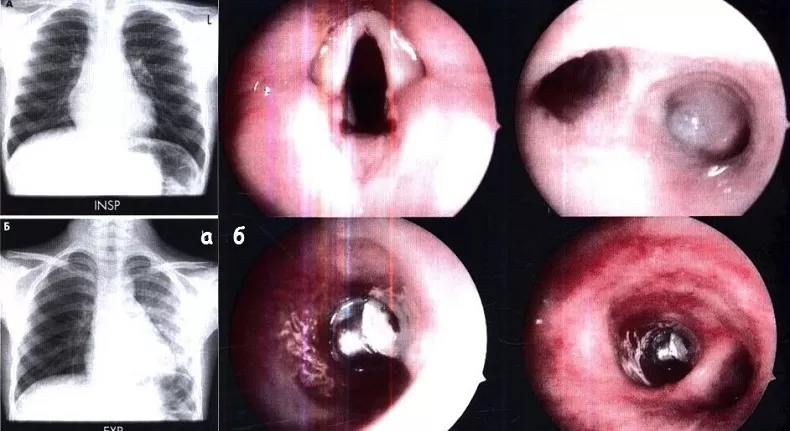

При обзорной рентгенографии органов грудной клетки можно увидеть прямые признаки инородного тела (если оно рентгеноконтрастное, что бывает примерно в 25% случаев), или косвенные признаки: нарушение проходимости дыхательных путей, локализованные бронхоэктазы,  особенно у лиц с органическими инородными телами.  В то же время у 14-35% пациентов рентгенологических изменений может не быть. [7] Компьютерная томография является более чувствительным методом диагностики, помогает в планировании бронхоскопии и может быть использована при подозрении на аспирацию. Но несмотря на достаточно высокую чувствительность метода, в некоторых случаях могут быть ложноотрицательные результаты обследования. Таким образом, даже при отсутствии рентгенологических проявлений при подозрении на инородное тело должна быть выполнена бронхоскопия  [4,6].

Бронхоскопия является золотым стандартом диагностики и лечения инородных тел нижних дыхательных путей. Впервые успешное удаление инородного тела бронхов  было выполнено Густавом Киллианом в 1897 году. Он извлек кости из бронхов у 63-летнего мужчину с помощью эзофагоскопа,  ознаменовав начало эры ригидной бронхоскопии. Но введенный в клиническую практику в 1970х годах метод гибкой бронхоскопии постепенно   вытеснил ригидную бронхоскопию, и сейчас является методом первой линии у большинства взрослых пациентов, позволяющей в большинстве случаев выявить и извлечь инородное тело нижних дыхательных путей [3].